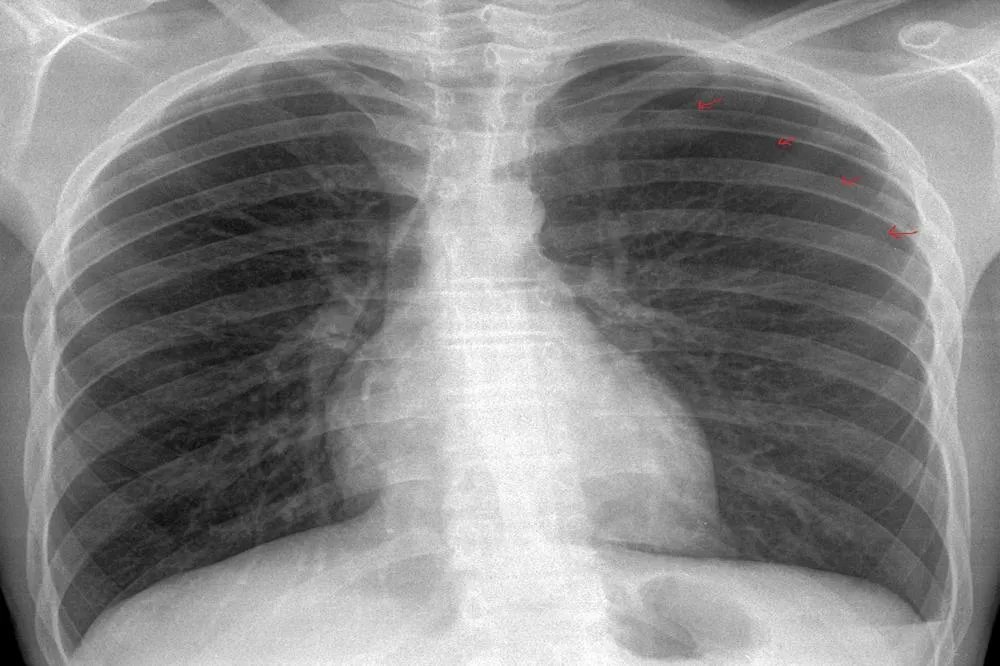

正常人的胸片图片

正常人胸片示意图意义胸部X线检查是临床上应用最广泛的检查之一。可以筛选出很多疾病,比如肿瘤疾病。很多老年人因为咳嗽去医院做胸部X光检查,才发现已经存在可疑肿瘤,然后可以进一步做胸部CT检查,进一步确诊。慢性阻塞性肺疾病患者突然胸痛,可能是气胸。这时候查体一般能做出诊断,快速胸片也能确诊。高血压心脏病患者,胸部X光显示心脏增大。病人可能遭遇车祸,可能导致肋骨骨折。这时候胸片就可以确诊了,必要时还需要做胸部CT进一步确诊。年轻人淋雨感冒后出现咳嗽、胸痛、咳痰等症状,怀疑是肺炎。胸片上可见大量高密度影,可确定为肺炎。